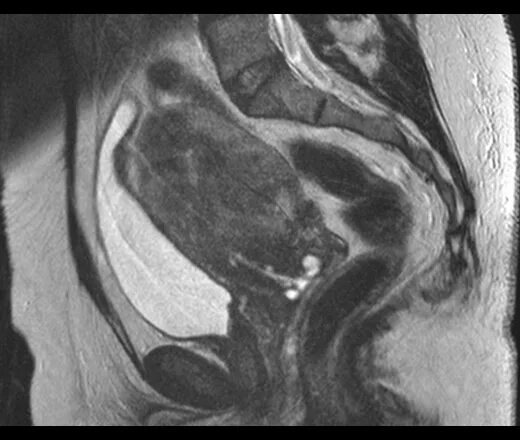

Мрт малого таза в нижнем новгороде